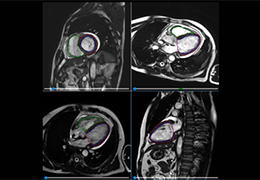

ART-Plan™ Artificial Intelligence Contouring